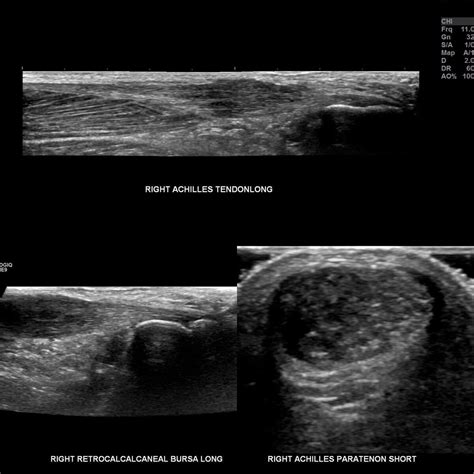

Diagnosing Tendonitis

Diagnosing tendonitis typically involves a physical examination and a review of your medical history. Your healthcare provider may ask about your symptoms, the activities that aggravate the pain, and any recent injuries. Imaging tests, such as X-rays, ultrasound, or MRI, may be ordered to rule out other conditions and confirm the diagnosis.

Diagnosing Tendinosis

Diagnosing tendinosis involves a physical examination and a review of your medical history. Your healthcare provider may ask about your symptoms, the activities that aggravate the pain, and any recent injuries. Imaging tests, such as ultrasound or MRI, can help confirm the diagnosis by revealing degenerative changes in the tendon.